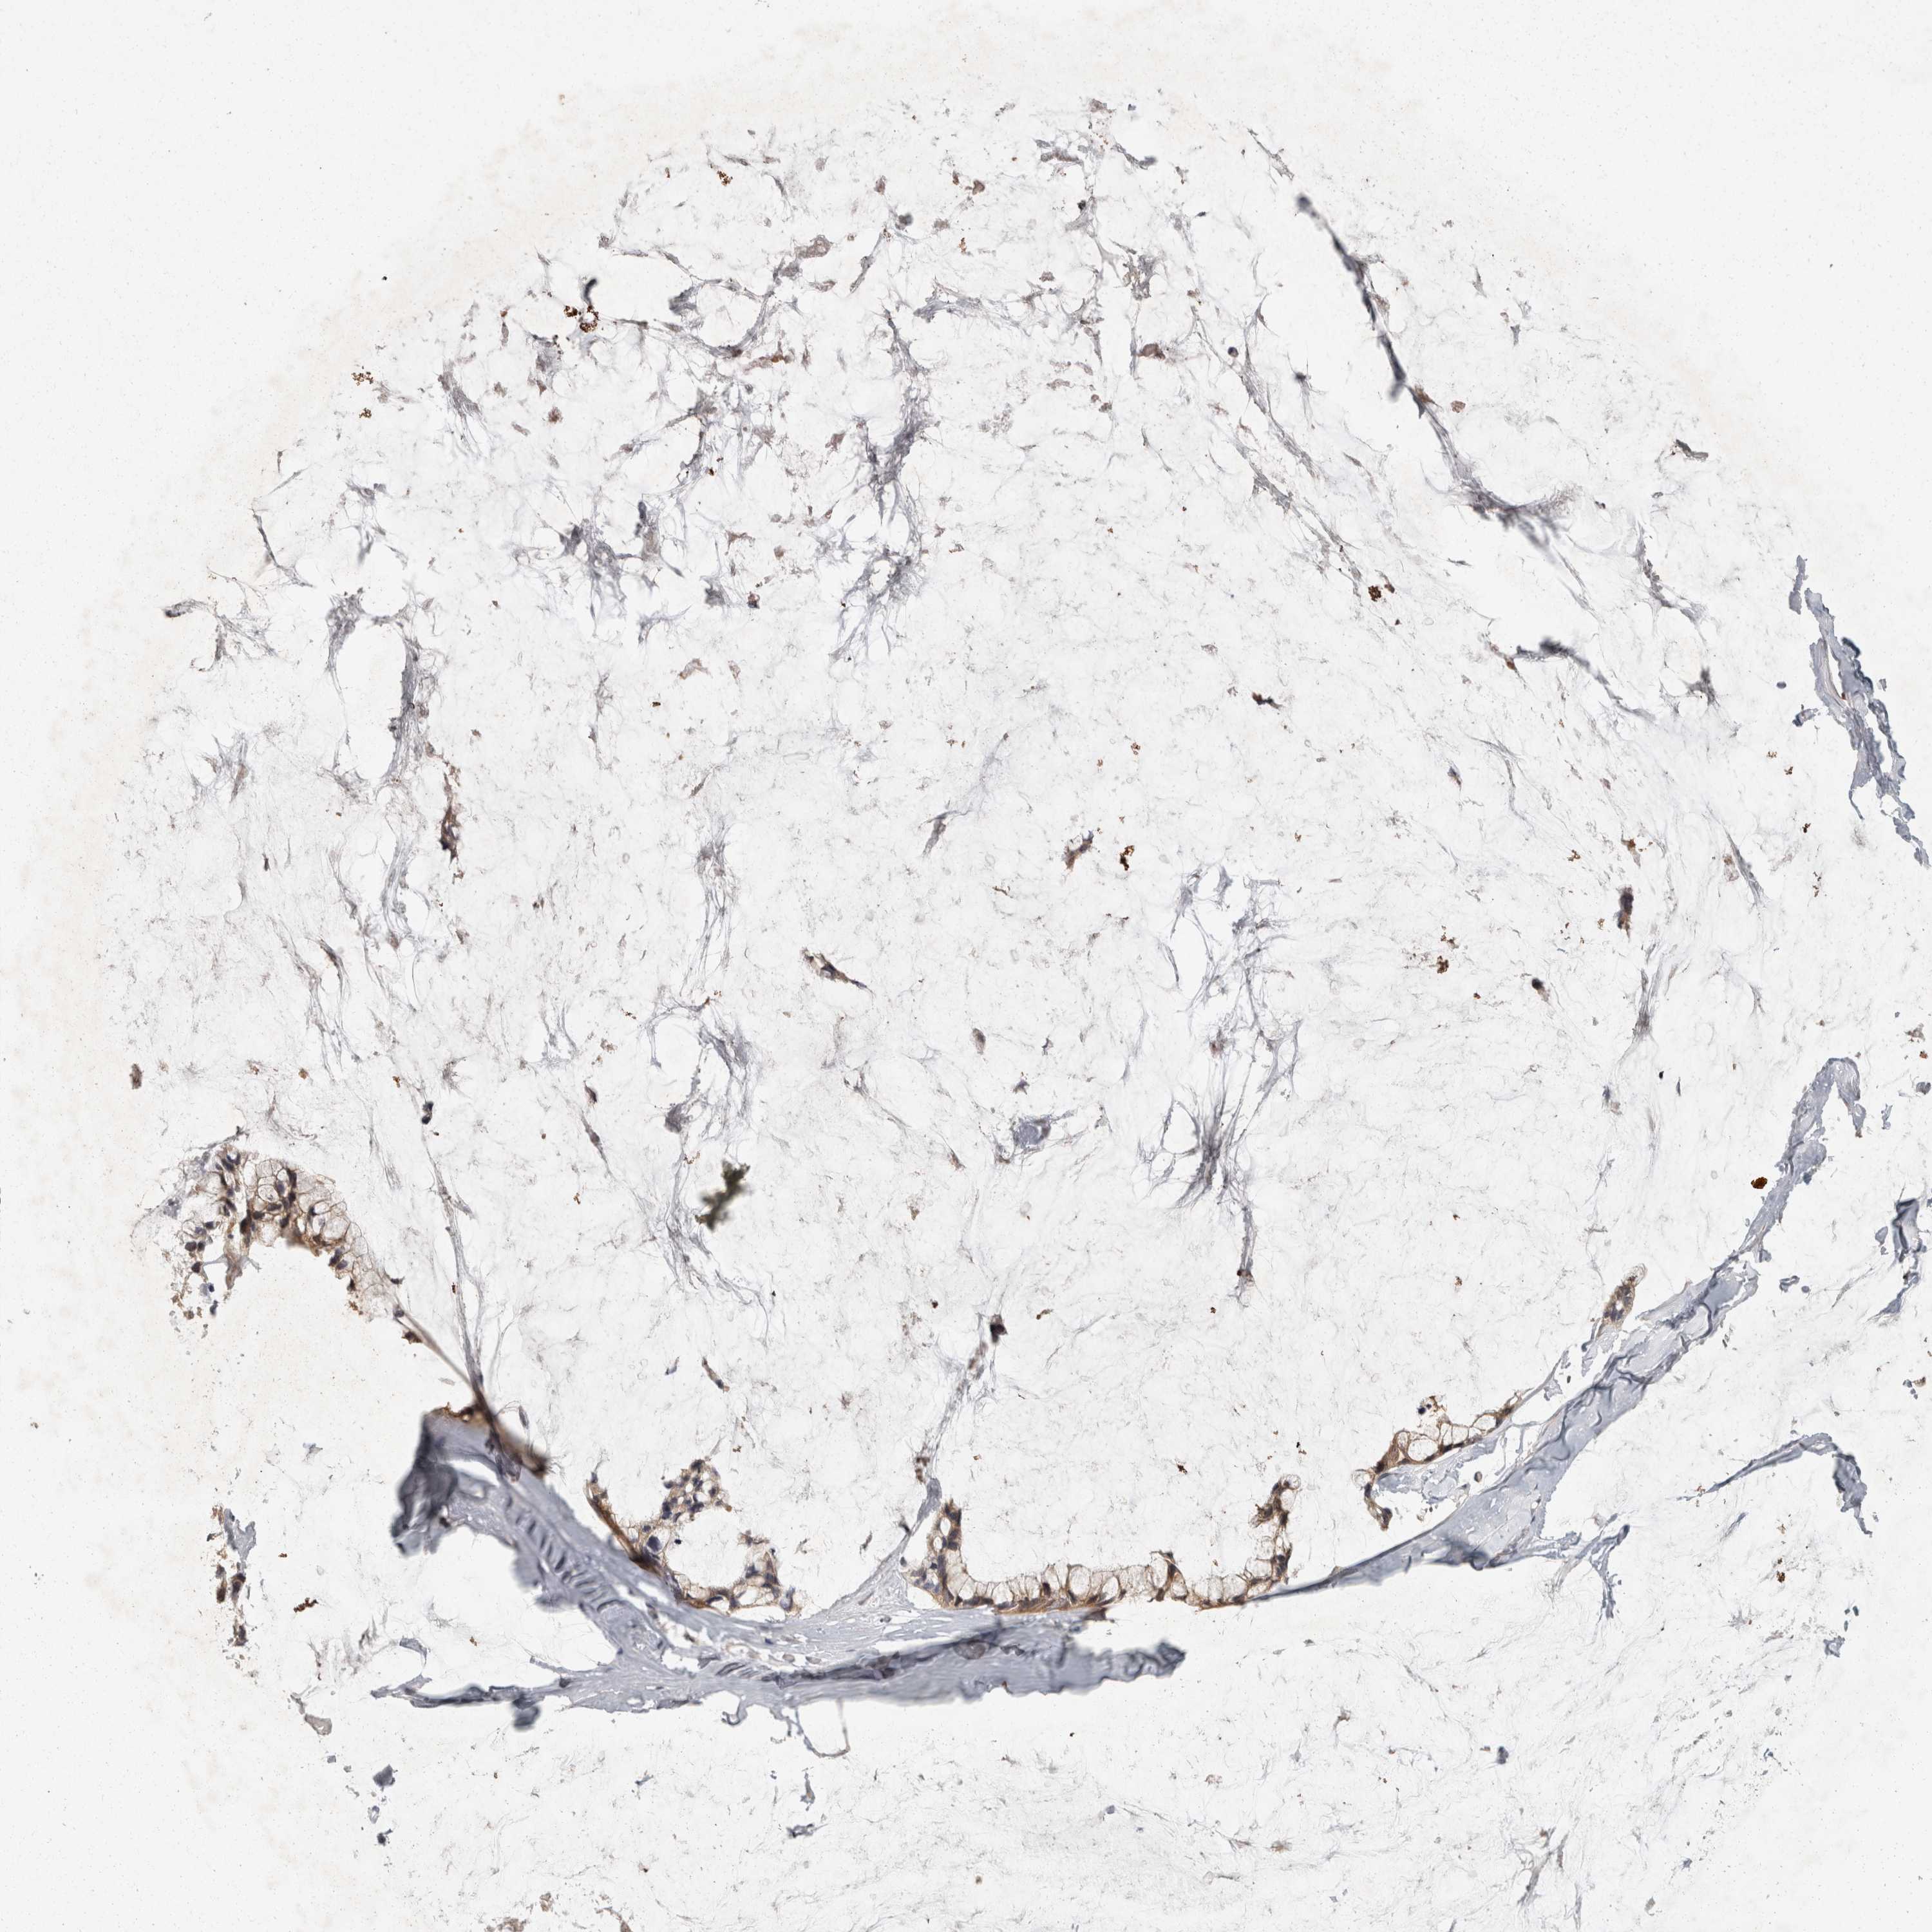

OVARIAN CANCER - Protein expressioni

A mouse-over function shows sample information and annotation data. Click on an image to view it in a full screen mode. Samples can be filtered based on level of antibody staining by selecting one or several of the following categories: high, medium, low and not detected. The assay and annotation is described here.

Note that samples used for immunohistochemistry by the Human Protein Atlas do not correspond to samples in the TCGA dataset.

Antibody stainingi

Antibody staining in the annotated cell types in the current human tissue is reported as not detected, low, medium, or high, based on conventional immunohistochemistry profiling in selected tissues. This score is based on the combination of the staining intensity and fraction of stained cells.

Each image is clickable and will lead to virtual microscopy that enables deeper exploration of all samples and also displays staining intensity scores, fraction scores and subcellular localization as well as patient and tissue information for each sample.

Antibody HPA025736

Antibody CAB021106